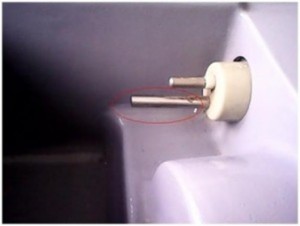

– اختلال یا خرابی سنسورها : در صورتی که سنسور دما تماس درستی با پوست کودک نداشته باشد، دمای خوانده شده کمتر از دمای واقعی خواهد بود و در نتیجه گرمای بیشتری توسط دستگاه تولید شده که باعث ایجاد گرمای بیشتر از حد در محفظه و ایجاد مشکلات ناشی از آن می شود. از طرف دیگر، اتصال محکم سنسور نیز باعث ایجاد حساسیت و آسیب پوستی نوزاد می شود. در نتیجه لازم است که دمای کودک مرتب توسط کاربر چک شود. سنسور دمای محفظه نیز بایستی چک شود(به همان روشی که قبلا در مورد تست ایمنی نوزاد ذکر شد) در صورت لازم سنسور باید تعویض شود.